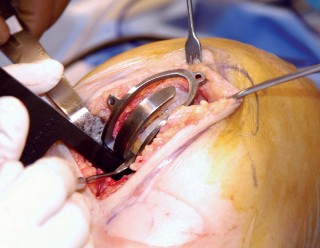

1. التخطيط قبل الجراحة

-

القوالب المسبقة (Preoperative Templating):

يتم استخدام الأشعة السينية لتحديد حجم وموضع المكونات المزروعة بدقة قبل الجراحة.

2. الوضع الجراحي والتعرض

- الوضع: يُوضع المريض في وضع الاستلقاء (Supine positioning) مع وضع كيس رمل أسفل الركبة أو حامل للساق يسمح بثني وفرد الركبة. يجب أن يكون الوضع مماثلاً لوضع جراحة TKA، مع استعداد لتحويل الإجراء إلى TKA إذا لزم الأمر.

- العاصبة (Tourniquet): تُستخدم عاصبة وتُوضع في أعلى الفخذ لتقليل النزيف.

-

الشق الجراحي:

يُستخدم شق طولي في الجانب الإنسي (الداخلي) من الركبة. يجب أن يكون الشق كبيرًا بما يكفي لتوفير رؤية جيدة للمفصل الرضفي الفخذي وإمكانية التحويل إلى TKA.

- فتح المفصل (Arthrotomy): يكون الفتح خطيًا وموازياً لألياف الوتر الرضفي، ويمتد إلى عظم الظنبوب وإلى الجزء السفلي من الرضفة.

- تحرير الأنسجة الرخوة: يتم قطع الغضروف الهلالي لتحرير الأنسجة الرخوة من عظم الظنبوب، ويتم تطوير سديلة تحت السمحاق في نمط دائري حول الظنبوب. يُمدد هذا التحرير خلفيًا لضمان توازن الأربطة.

-

تصحيح التشوه:

الهدف هو تحقيق تصحيح طفيف للتشوه، مع وجود رخاوة كاذبة طفيفة عند تطبيق ضغط تفحجي في نهاية الإجراء. يجب تجنب التصحيح المفرط.